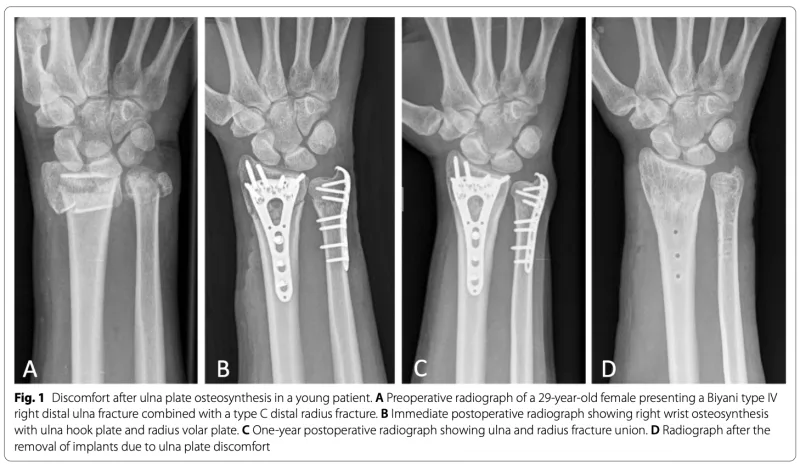

13時半から1年前に橈骨遠位端粉砕骨折, 尺骨茎状突起の手術を行った中高年患者さんに対する骨内異物除去術.